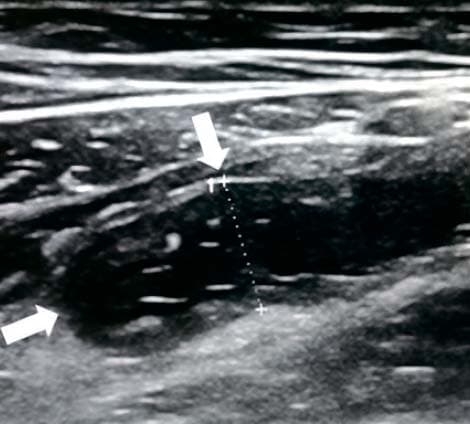

Аппендикс считается расширенным, если под действием компрессии его наружный переднезадний размер, измеренный при поперечном сканировании, более 6 мм (см. рис. 3).

Рисунок 3. Определение диаметра аппендикса.